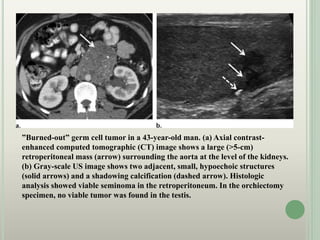

”Burned-out” germ cell tumor in a 43-year-old man. (a) Axial contrast-

enhanced computed tomographic (CT) image shows a large (>5-cm)

retroperitoneal mass (arrow) surrounding the aorta at the level of the kidneys.

(b) Gray-scale US image shows two adjacent, small, hypoechoic structures

(solid arrows) and a shadowing calcification (dashed arrow). Histologic

analysis showed viable seminoma in the retroperitoneum. In the orchiectomy

specimen, no viable tumor was found in the testis.